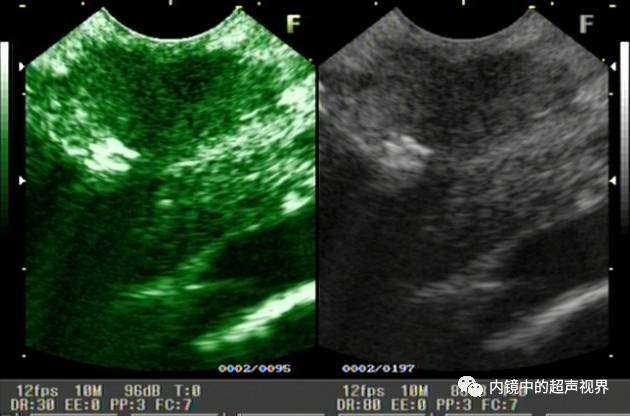

我现在使用的超声内镜DR可调节范围为30-90。以下三张图片显示的是同一个胰头肿物,肿物回声与胰腺回声非常接近,DR分别为90、70、40,其它参数相同,您更喜欢哪一张。

胰头占位